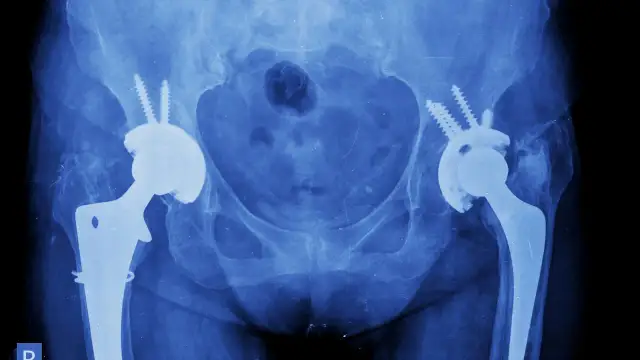

Kompleksowy przewodnik po rehabilitacji po endoprotezie biodra. Poznaj etapy, harmonogram, zakazy i ćwiczenia w domu. Wróć do sprawności bezpiecznie!

Poznaj etapy rekonwalescencji po endoprotezie biodra: od szpitala do pełnej sprawności. Dowiedz się, co wpływa na czas powrotu do życia i uniknij błędów.